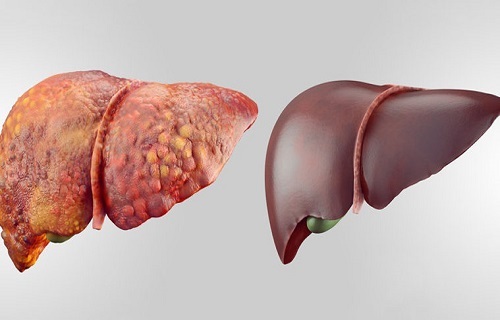

عامل اصلی ابتلا به کبدچرب را بشناسید

آفتاب نیوز : دکتر علی بهشتی نامدار با اشاره به اینکه کبد دومین عضو بزرگ در بدن انسان است که…